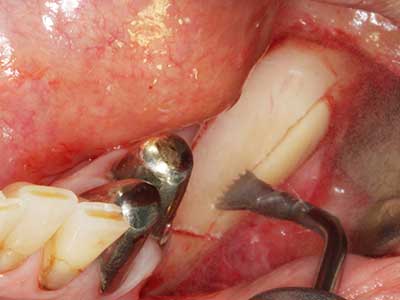

La piezochirurgia presenta altri vantaggi per quanto riguarda la raccolta di blocchi ossei. Oltre all'elevata precisione dell'osteotomia appena descritta, l'utilizzo di puntine per sega molto sottili permette di minimizzare in maniera significativa la perdita di materiale. È molto probabile che si verifichi una maggiore perdita di materiale durante la raccolta utilizzando puntine di strumenti più spessi, in particolare delle frese Lindemann (Lakshmiganthan, Gokulanathan et al. 2012). La separazione basale, necessaria in particolare per i trapianti di blocchi nella zona retromolare, viene semplificata grazie a seghe specificatamente progettate di forma rettangolare; di conseguenza la piezochirurgia è considerata una procedura precisa, semplice e sicura per la raccolta di blocchi di osso nella zona retromolare (Happe 2007) (figg. 1-12).